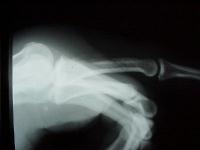

This gentleman presented with a draining sinus on the dorsal aspect of his proximal phalanx, about one month after sustaining a clenched fist bite injury.  He could not clearly recall details of his initial treatment.

Radiographs show evidence of osteomyelitis with bone erosion and subperiosteal bone formation (arrows).

The patient was unreliable as an outpatient, and refused hospitalization, and was treated with a metacarpophalangeal joint disarticulation.